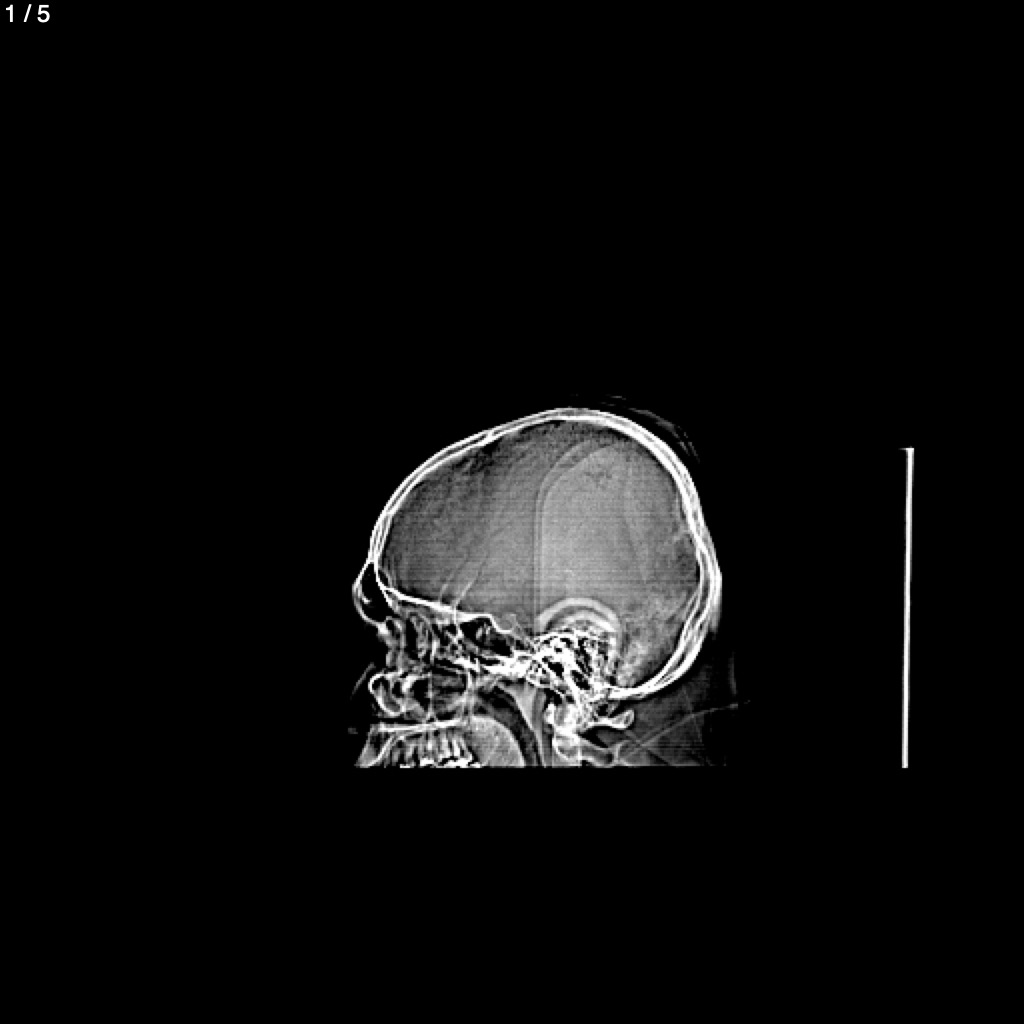

Rufino Eduardo Tovar Lopez - Cabeza Simple_Craneo (Adulto)